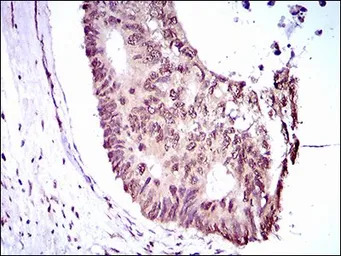

IHC-P analysis of rectum cancer tissue using GTX60769 KLF1 antibody [1B6A3].

IHC-P analysis of cervical cancer tissue using GTX60769 KLF1 antibody [1B6A3].